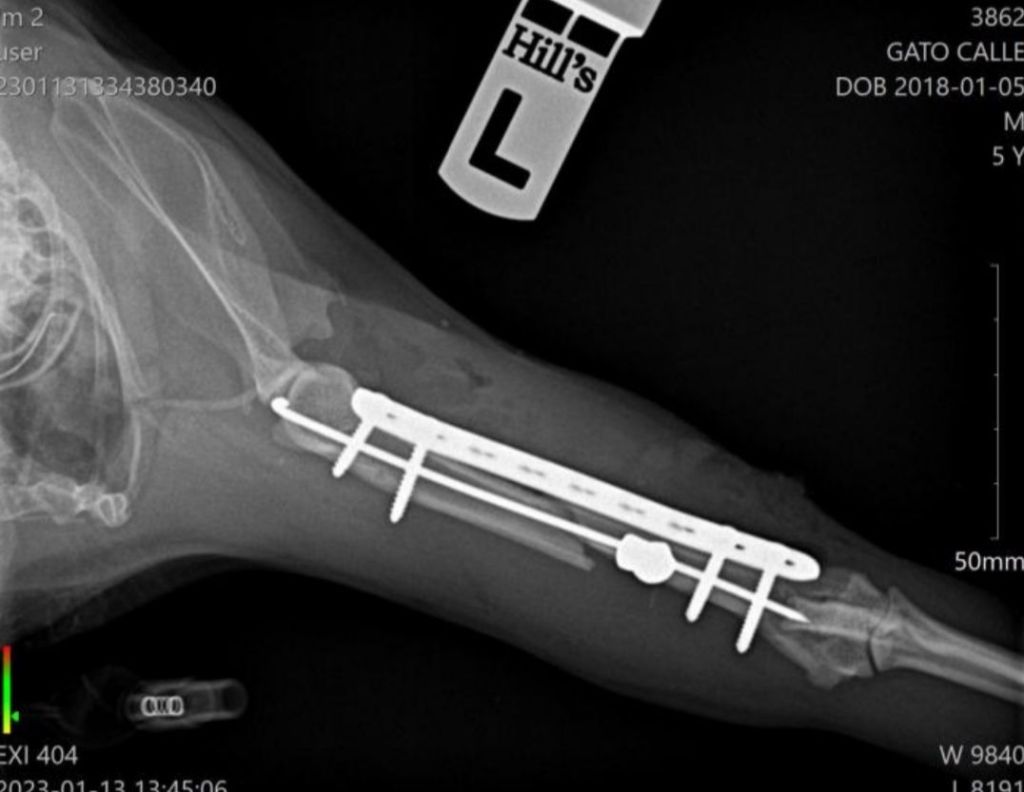

Desde la Asociación harán todo lo posible para intentar salvar su patita y por ello ha sido necesario someterle a una intervención quirúrgica.

Lin permanece ahora recuperándose con analgesia y antibiótico a la espera de ver la evolución. Según indica el informe médico se trata de “fractura medial oblicua de húmero como consecuencia de disparo por arma de fuego con material alojado en la parte caudal del músculo tríceps braquial. Reducimos la fractura bajo anestesia general y la fijamos con aguja centromedular y placa bloqueada”

*Se aportan fotos del gato y radiografías de la pata.